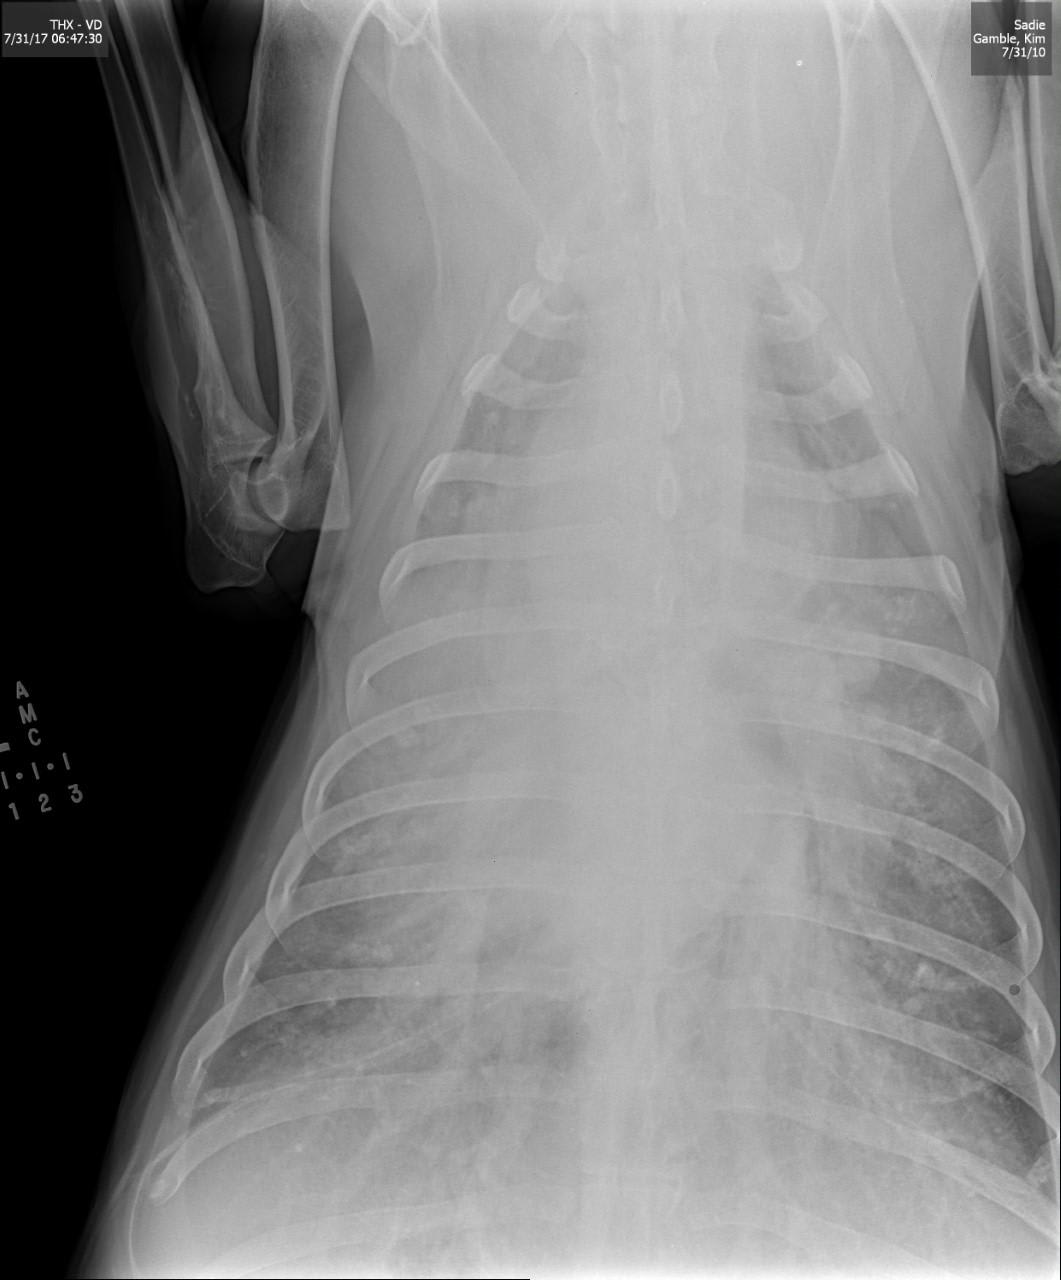

Pet's info: Dog | German Shepherd | Female | spayed | 7 years and 10 months old | 85 lbs

7 YR OLD GERMAN SHEPHARD, FLUID IN BELLY, HEAVY PAINTING, RAPID HEARTBEAT,STILL EATS, NO POOP, NO VOMIT, VET SAID SHES DYING SOON, BUT NO BLOODWORK WAS DONE AND GIVEN PREDNISOLONE & CLAVAMOX. HE SAID MAYBE CANCER, OR HEART, OR CIRVO SHES GETTING WORSE STILL HAVE NO ANSWER TO WHAT IS THE MATTER TO START TRYING TO HELP HER

Hi and thanks for using Petco Pet Education Center, formerly Petcoach! I'm so sorry to hear about Sadie. This sounds very serious. Anytime there is fluid in a body cavity, the situation is serious. I would need to know more to give a better answer but in a German Shepherd dog of this age, one thing is likely and that is a tumor of the spleen. These are called hemangioma or hemangiosarcoma or it could even be a hematoma or benign growth on the spleen that is bleeding. These are usually a surgical emergency especially if they are bleeding into the abdomen. Depending on what type of Other reasons for fluid to accumulate in the belly would be heart disease, liver disease, other tumors or masses in the abdomen, kidney problems. A tap of the abdomen (abdominocentesis) would reveal what the fluid is and maybe how to proceed. I would advise taking Sadie back to your vet or taking her somewhere else for a second opinion if you want to try to do something with her. And I would advise this as soon as you can get her there. Not sure if surgery is an option and that would depend on her condition and what you do comfortably afford for her. I'm so sorry again and I really hope that she gets better very soon.